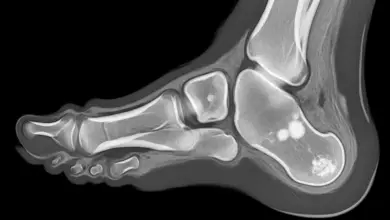

Patologias e Condições Gerais  Artrose do tornozelo: causas, sintomas e tratamentoA artrose do tornozelo é o desgaste progressivo da cartilagem que reveste a articulação. Quando essa camada se torna fina,… Leia mais »